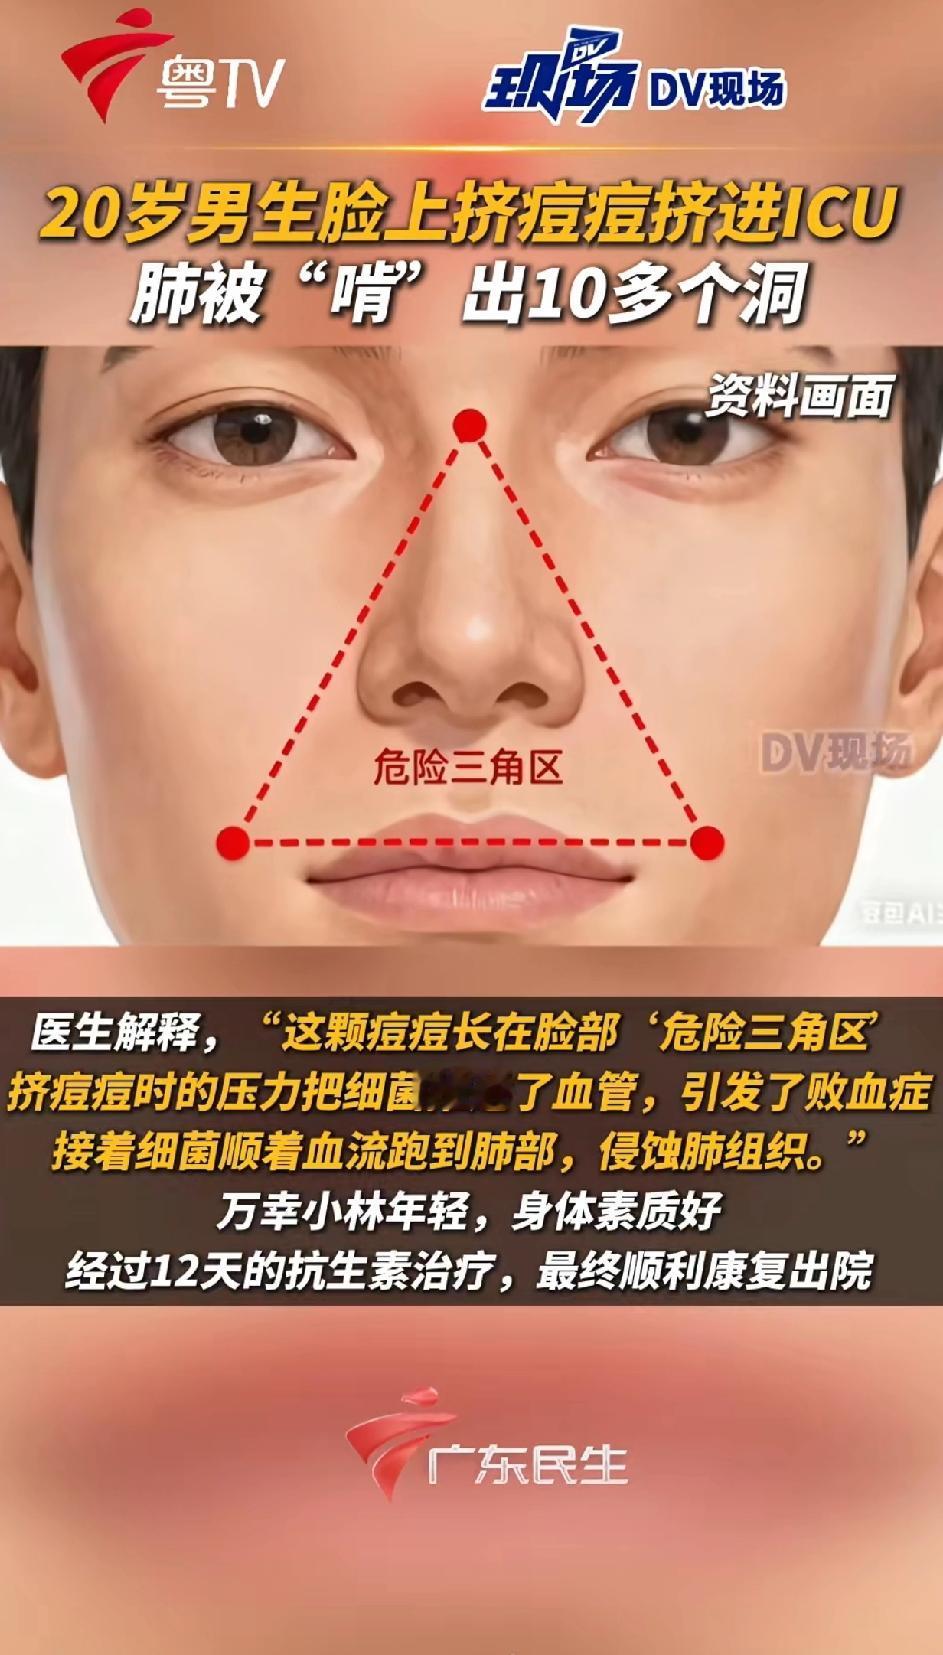

挤一颗痘痘竟致肺里现十几个空洞!大二学生的惨痛教训 20岁的大二学生小林为备考熬夜后,脸部冒出一颗黄豆大小的红肿痘痘。因觉得影响美观,他未洗手便对着镜子将其挤掉,当时看着脓水流出还倍感清爽。 然而几天后,痘痘不仅持续化脓,小林还出现发烧、咳嗽、咳痰等症状,退烧药仅能暂时缓解不适,右下胸更是传来针刺般的疼痛,深呼吸、咳嗽时疼得直冒冷汗。熬至第三天,体温升至39℃的小林紧急前往宁波大学附属第一医院就诊。 接诊的丁群力主任医师通过CT检查发现,小林肺内出现十几个空洞,部分肺组织已坏死,确诊为血源性肺脓肿。细菌培养和基因检测显示,其血液中检出的金黄色葡萄球菌是“元凶”——该细菌原本存在于皮肤表面,而小林挤的痘痘位于脸部“危险三角区”,未洗手的操作让细菌在挤压压力下进入血管引发败血症,进而随血流侵入肺部,侵蚀肺组织导致严重感染。医生提醒,脸部危险三角区的痘痘切勿随意挤压,皮肤出现感染需及时科学处理,避免引发致命风险。